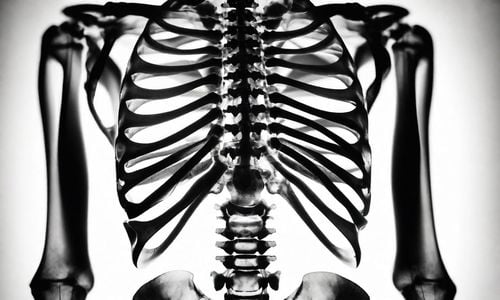

Gãy xương là sự phá hủy đột ngột các cấu trúc bên trong xương gây ra tổn thương và làm gián đoạn quá trình truyền lực qua xương hay chính là sự mất liên tục và hoàn chính của xương. Gãy xương có thể do nhiều nguyên nhân gây ra trong đó gãy xương bệnh lý có thể xảy ra do những nguyên nhân tiềm ẩn khác nhau.

Gãy xương bệnh lý là tình trạng một xương bị gãy tại vị trí mà vốn đã bị yếu từ trước đó do tình trạng bệnh tật nên dễ gãy hơn thông thường. Các nguyên nhân làm suy yếu xương có thể là loãng xương, khối u, nhiễm trùng hoặc các rối loạn di truyền và các bệnh lý khác.

Cơ chế của gãy xương bệnh lý: một trường hợp bị gãy xương thông thường là do va chạm tác động đột ngột gặp trong thể thao, tai nạn lao động hoặc tai nạn giao thông. Tuy nhiên gãy xương bệnh lý lại có thể xảy ra trong một hoạt động bình thường hàng ngày như đánh răng, tắm hoặc đi bộ do các xương thực hiện vận động đã rất yếu và dễ gãy.